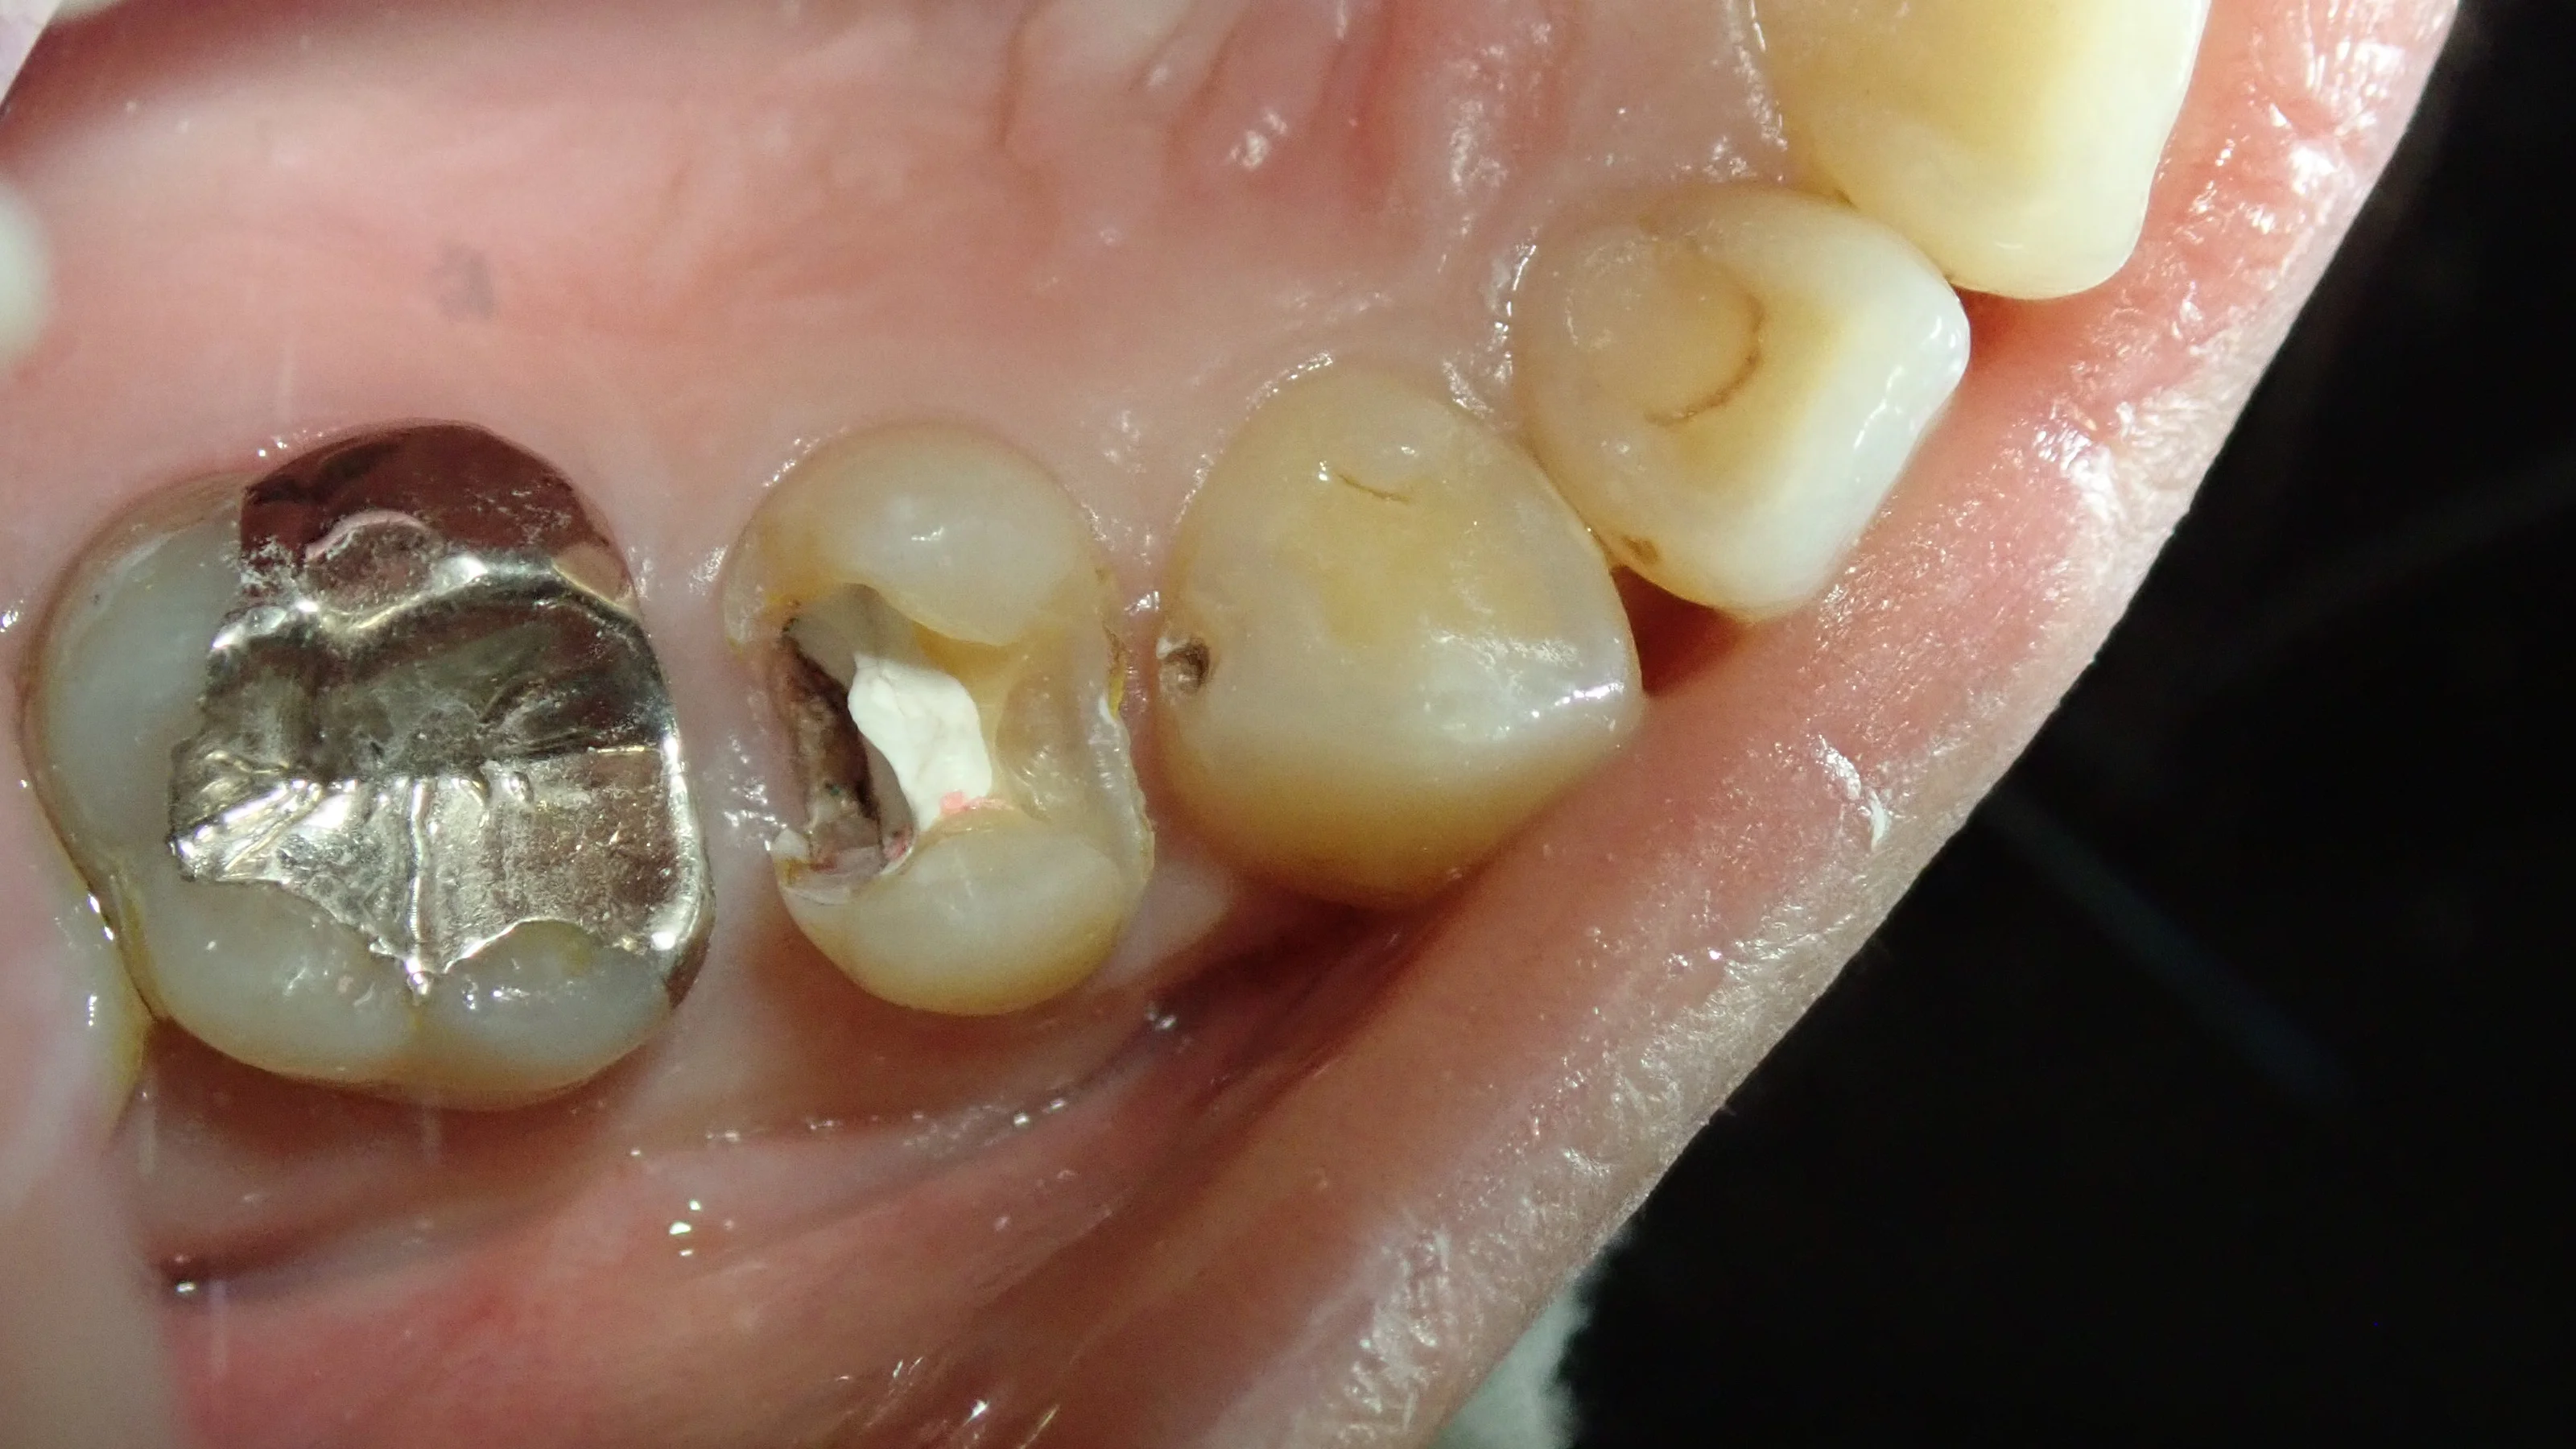

では、症例写真に移ります。

白い詰め物が入っていますが、前後に大きな隙間がある状態で詰められています。

そのせいで、前後の歯に虫歯が出来てしまっている状態でした。